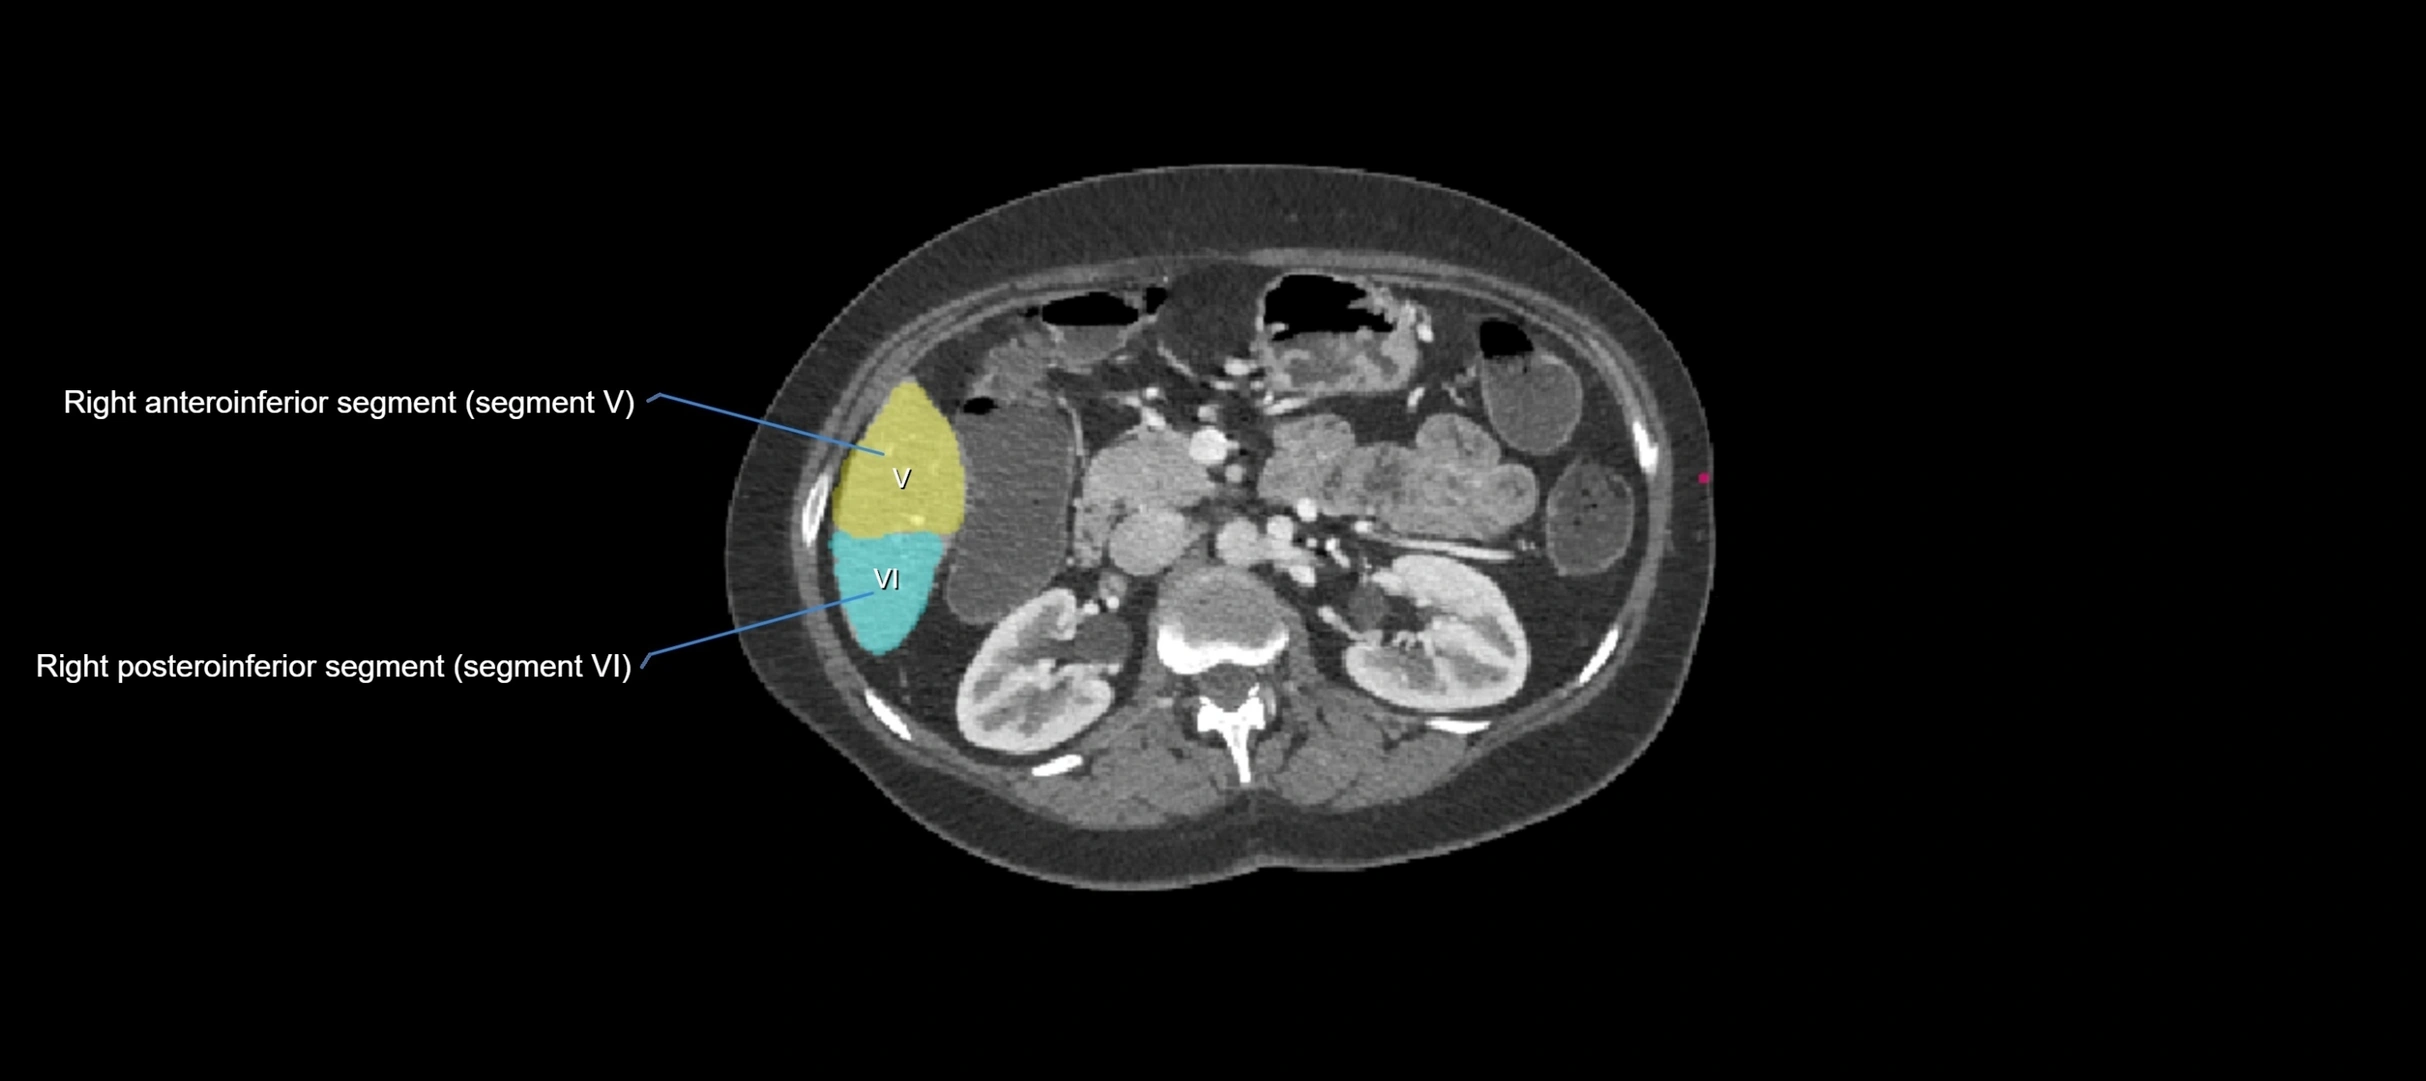

CT Image

image